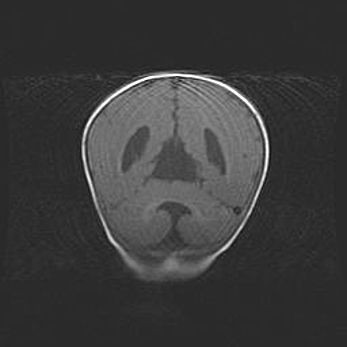

Сообщающаяся гидроцефалия. Кистозная энцефаломаляция головного мозга.

Возраст: 3 месяца 4 дня

Вес: 3100 г

Пол: женский

Окружность головы: 34 см

Срок гестации: 31 неделя

Кистозная энцефаломаляция головного мозга - одна из форм поражения головного мозга в детском возрасте. Характеризуется возникновением множественных и распространённых кист в коре, белом веществе и подкорковых образованиях головного мозга у плодов, новорождённых и детей раннего возраста. Развитие кистозной энцефаломаляции связано с внутриутробной асфиксией и гипотонией, родовой травмой, тромбозом синусов, пороками развития сосудов, инфекциями, сепсисом и другими причинами. Наиболее значимые инфекционные агенты: вирусы простого герпеса, цитомегалии, краснухи, токсоплазмы, энтеробактерии, золотистый стафилококк и другие.